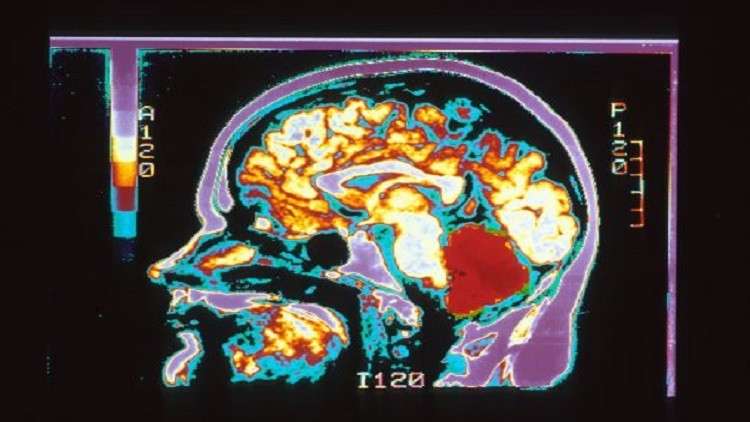

ما هي أوجه الاختلاف بين دماغ الرجل والمرأة!

منوعات - الكوثر: أجرى علماء جامعة كامبريدج البريطانية دراسة علمية هي الأكبر والأوسع لمعرفة أوجه الاختلاف بين دماغ الرجل والمرأة، استنادا إلى معطيات لأكثر من 671.6 ألف شخص، بحسب صحيفة التايمز.

ويؤكد العلماء على أن بنية دماغ الرجل تختلف عن بنية دماغ المرأة، وقد أكدت نتائج هذه الدراسة نظريتان بهذا الشأن.